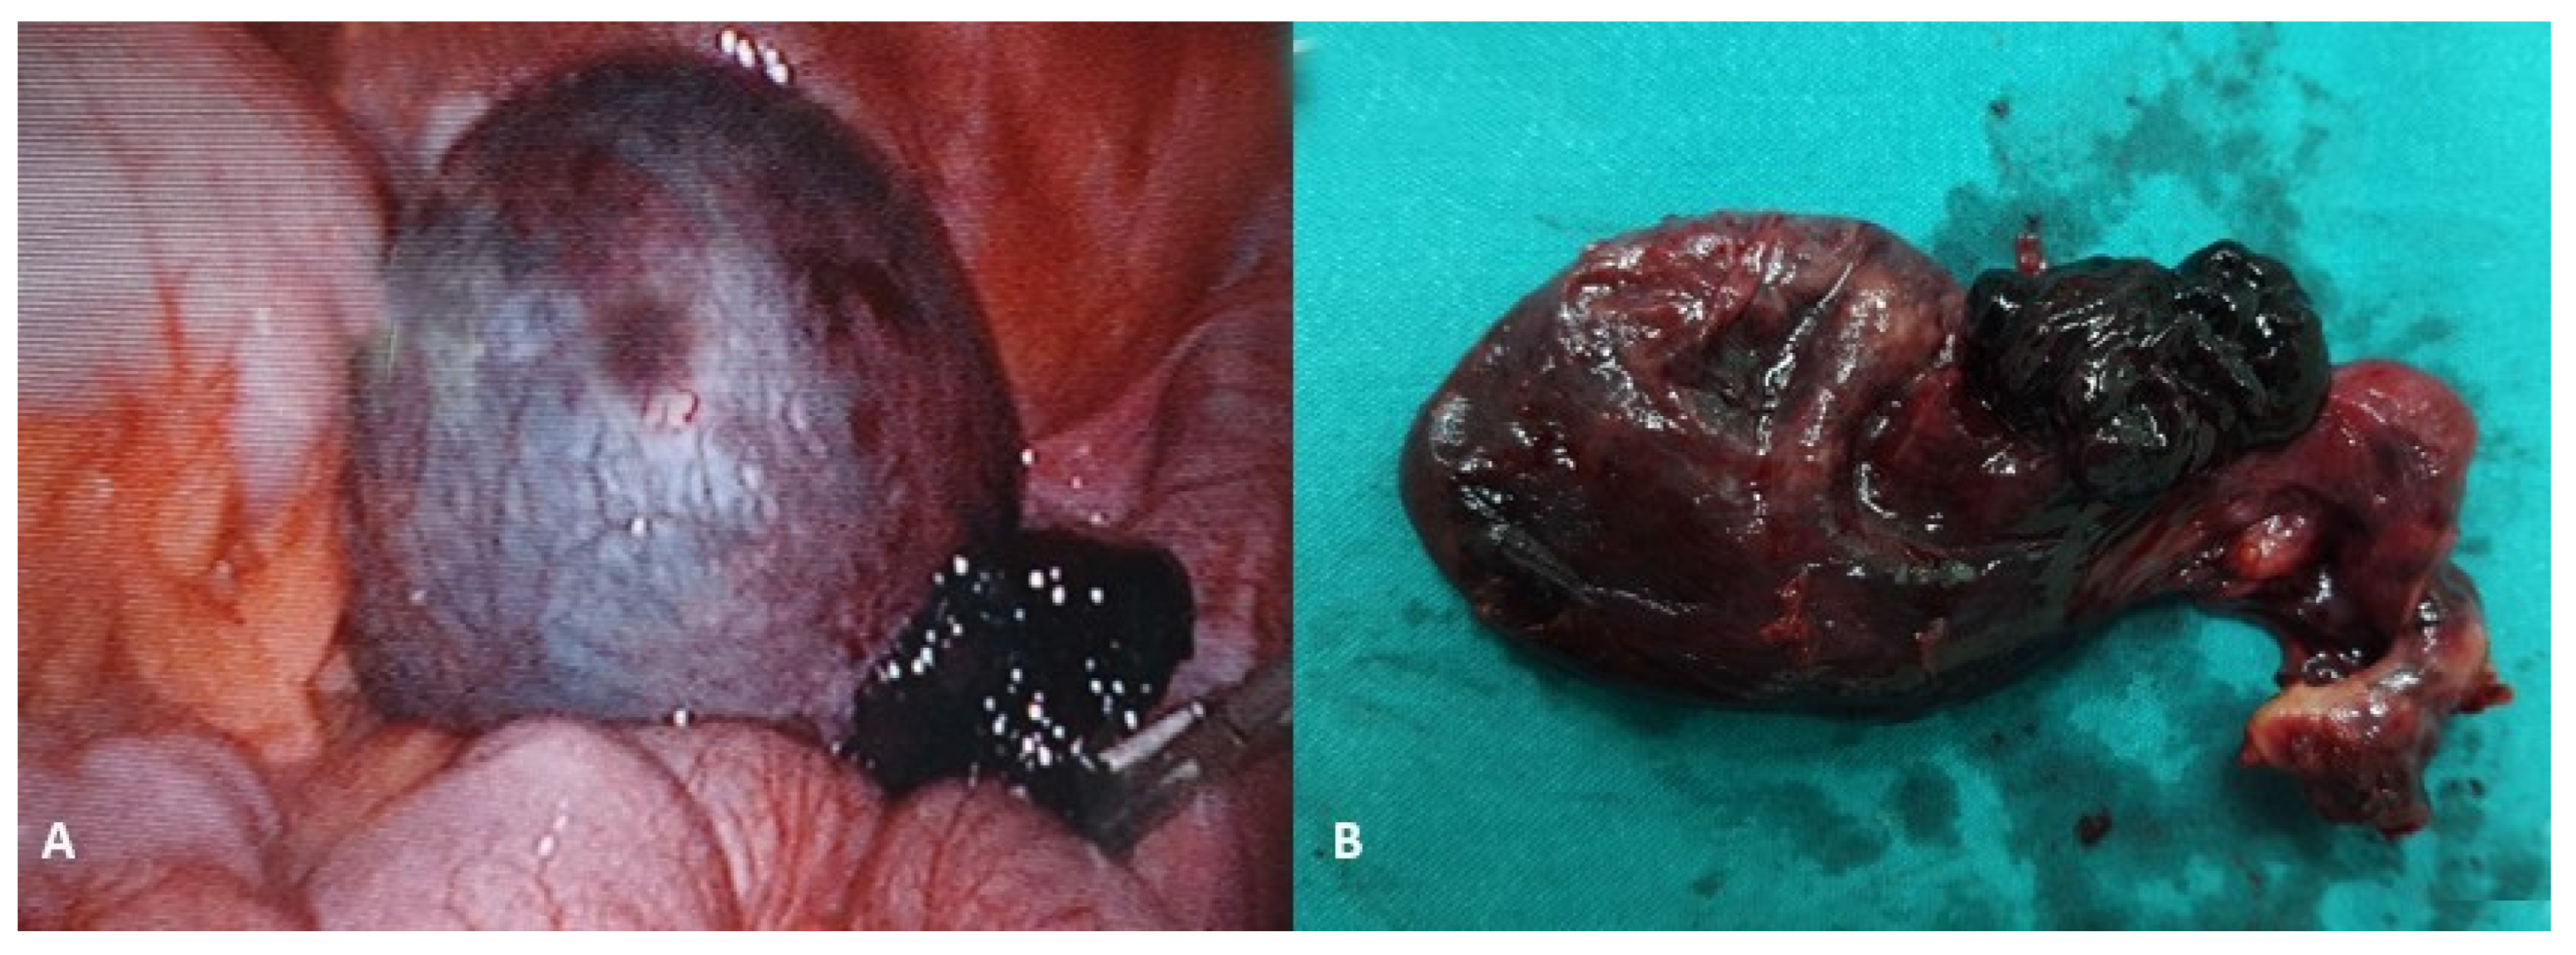

The spontaneous regression of ovarian cysts usually occurs after birth, usually by 6 months or even 1 year of age [26,27]. The rate of spontaneous regression tends to decrease with increasing cyst size. The rate ranges from approximately 90% for cysts ≤ 2.9 cm to 20% for those ≥ 6 cm [28,29]. Accordingly, ultrasound observation after the child’s birth is recommended every 4–6 weeks. For cysts that enlarge or persist for 4 months or more, continued observation, aspiration, or surgical removal (cystectomy) are all reasonable choices [30]. Aspiration is a possible choice for uncomplicated neonatal ovarian cysts that are ≥ 6 cm in diameter, provided they have not spontaneously regressed by four months. Should the cyst recur, it can be reaspirated or surgically removed (usually for neonatal ovarian cysts that are complex, symptomatic, or enlarging). Laparoscopic surgery is a recommended surgical approach, wherein ovarian tissue must be preserved as much as possible [11,30,31,32,33]. Ovarian torsion is the most common complication of ovarian cysts in infants (Figure 1), and it occurs mainly in cysts that begin to grow rapidly and their ultrasound features change. Also, the risk of ovarian torsion has been found to be more related to the length of the pedicle than to the size of the cyst itself [30,34,35].

Figure 1.

A 7-day-old female neonate presented with a large abdominal mass. (A) Laparoscopic examination revealed a necrotic, twisted, huge neonatal ovarian cyst measuring 6 × 5 × 4 cm; (B) Twisting of the ovarian pedicle by 720 degrees; (C) After decompression of the cyst, a laparoscopic salpingo-oophorectomy was performed due to the obvious necrosis of the ovarian tissue. Source: Archive of the Department of Pediatric Surgery, University Hospital of Split.